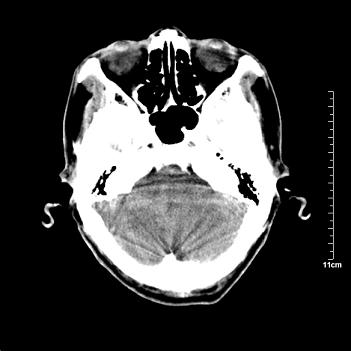

男性患者,72岁,近两天头晕来我院就诊。 因患者血压太高而未做增强,建议病人去市医院做mri检查。等得到mri随访结果再公布给大家。 测及左颞顶枕叶病灶ct值分别为5hu 30hu 729hu。

考虑左侧颞顶枕叶少突胶质细胞瘤。 今天随访患者手术病理结果 病理回报为胶质瘤2级 钙化

左侧颞顶枕叶大片状低密度影,呈均一水样密度,边界清楚,病灶边缘不规则片状钙化,左侧脑室后角扩大,中线结构未见移位,综合来看不像肿瘤,软化灶,钙化不好解释

左侧颞顶枕叶巨大囊性病灶,灶内见小片实性区且灶内及灶周围大量团块状钙化影,灶周水肿少.左侧室枕角内见环形钙化,可见较清晰前壁,钙化与室壁似有间隙.

考虑1寄生虫病2表皮样囊肿钙化3血管畸形,其他不排